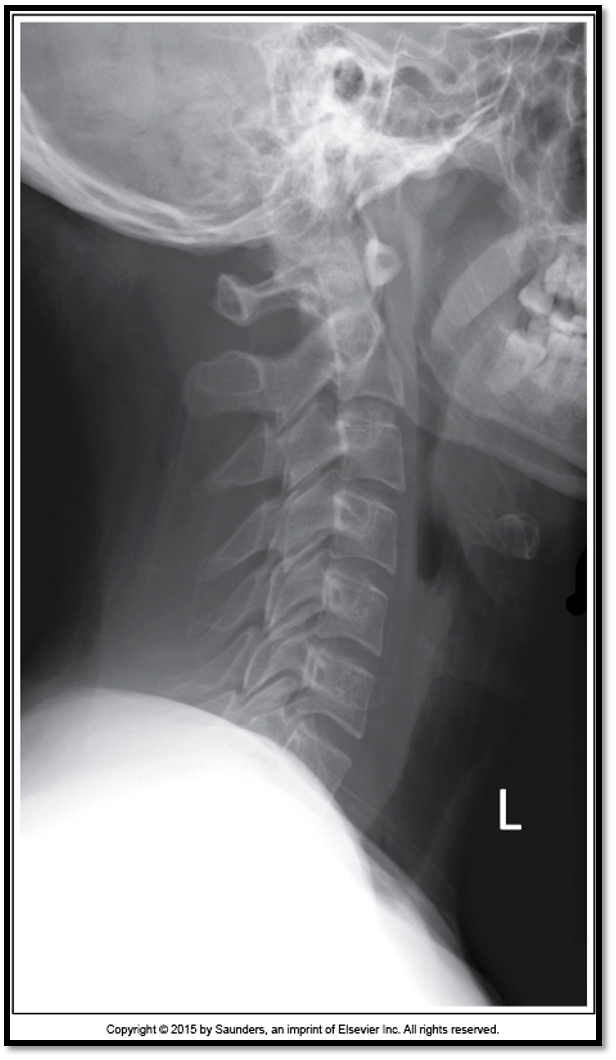

Lateral Cspine Criteria

• SI’d articular pillars and open zygopophyseal joints

• superimposition of posterior vertebral bodies

• mandible off spine

• open intervertebral spaces

• rotation issue: posterior borders arent aligned

• tilt issues: double lines at zygo joints

• need to do swimmers: cant see C7 and T1